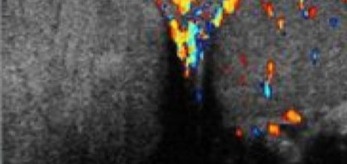

- Color Doppler U/S is the 1st line imagining modality; however, when torsion is considered, time should not be devoted to studies that may prolong the time to surgery… so call your urologist.

- U/S has been found to be useful at depicting whether there is arterial or venous compromise, yet it must still be remembered that it has a sensitivity of only 86-89%. So it isn’t perfect. Don’t ignore your clinical exam and instinct. 8-9

- If an ultrasound is equivocal, radionuclide scans may help reduce false negatives.